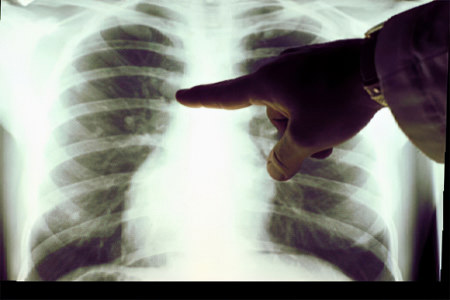

Окончательный диагноз ставится после рентгенологического исследования. На рентгеновских снимках в верхней или нижней доле легкого видны участки инфильтрации. Для получения более детальной информации может быть рекомендовано выполнение компьютерной томографии или бронхоскопии.

Первые симптомы левосторонней пневмонии могут быть замечены врачом во время осмотра пациента. При дыхательных движениях левая часть грудной клетки может отставать. При перкуссии над пораженными участками левого легкого слышен более короткий звук. Аускультация выявляет мелкопузырчатые хрипы и признаки крепитации.